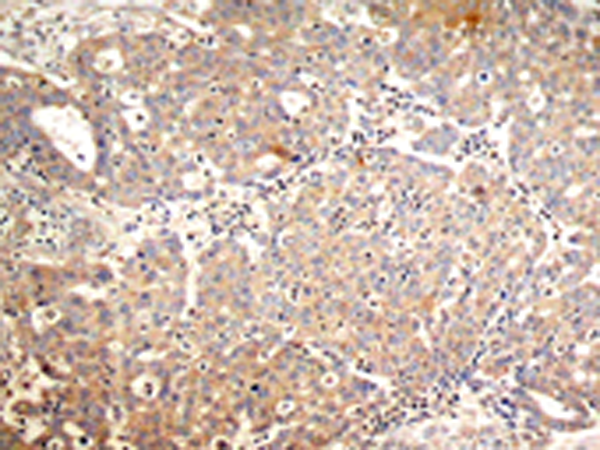

IHC positive control:

Human breast carcinoma